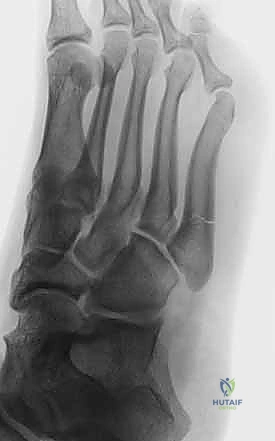

- التصوير بالأشعة السينية (X-rays): لأخذ فكرة أولية عن الكسر (زوايا بوهلر وجيسان - Bohler’s and Gissane’s angles).

- الأشعة المقطعية (CT Scan): وهي الخطوة الأهم والأكثر حيوية. توفر الأشعة المقطعية صوراً ثلاثية الأبعاد وتقاطعاً دقيقاً للكسر، مما يسمح بتصنيف الكسر (نظام ساندرز - Sanders Classification) وتحديد عدد الشظايا العظمية ومدى انزياحها داخل المفصل. بناءً على هذه الأشعة، يضع الدكتور هطيف خطته الجراحية الدقيقة.